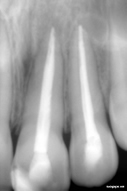

• But if the tooth decay is deep and it reach up to pulp then your whole tooth become infected up to the end of the root then we remove that pulp of tooth, clean the all canals in tooth and fill it by artificial nerves – “Gutta Purcha” like material and put a capping (Crown) over that. This procedure is called ROOT CANAL TREATMENT (R.C.T.)